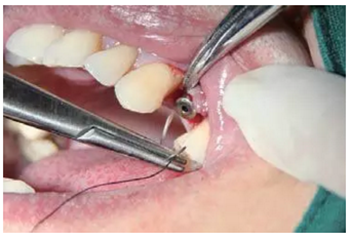

圖10 微創(chuàng)拔牙

逐級備孔

戴上導(dǎo)板逐級備孔,然后植入種植體,旋入覆蓋螺絲。

注意導(dǎo)板的就位要準(zhǔn)確不晃動,備孔時應(yīng)充分冷卻。

圖11 導(dǎo)板上備孔并植入植體,a.戴上導(dǎo)板,逐級備孔;b.植入種植體,并旋入覆蓋螺絲